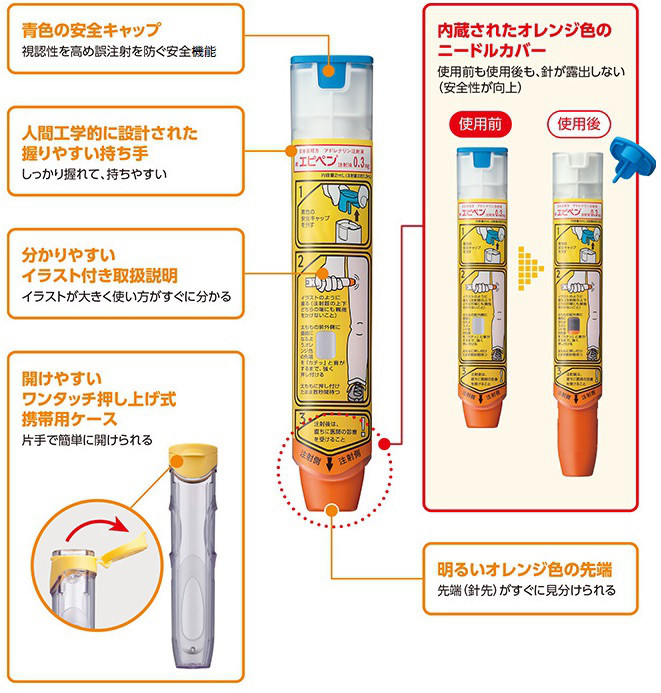

今回の少女が使用しているインスリン

グラルギン(グラルギンBS注キット)(持続型)

アスパルト(イノレット、ノボラピッドなど)(超速攻型)併用

食前に上記のインスリンを投与したが、食事摂取をしていないため低血糖発作を起こしている

処置

血糖測定(値は不明)

50%ブドウ糖注射液を静脈注射

低血糖発作(冷や汗、息切れ、動悸など)とは別に今回はアーモンドチョコレートを摂取したことによる、アレルギー発作が出現

アナフィラキシーショックとなっています

アナフィラキシーショックとは

急性で生命を脅かす可能性のあるIgE介在性のアレルギー反応

反応は以下により誘発される

・薬物

・植物

・タンパク

・動物毒

・ラテックス

好塩基球および肥満細胞上のIgEと抗原が相互作用すると、ヒスタミンおよびロイコトエリエンの放出、ならびに広範な平滑筋収縮(気管支収縮、嘔吐、または下痢などを来す)および血漿漏出を伴う血管拡張(蕁麻疹または血管性浮腫などを来す)を引き起こすその他のメディエータの放出を誘発する

症状

曝露後15分以内に現れ始め、皮膚、上気道、下気道、心血管系、または消化管に及ぶ。1ヶ所以上の部位に及ぶことがあり、症状は必ずしも軽度から重度に進行することはないが、個々の患者は典型的にはその後の曝露に対して同じ反応を起こす。

症状は軽度から重度まで様々である。

徴候には、低血圧、頻脈、蕁麻疹、血管性浮腫、呼気性喘鳴、吸気性喘鳴、チアノーゼ、および失神などがある。数分以内に死亡することがある。

少女は元々、アーモンドアレルギーがありアナフィラキシーショックを起こした経緯あり

少女の症状

発汗

蕁麻疹

喘鳴(気道閉塞)

チアノーゼ

血圧低下など

上記アナフィラキシー症状あり

処置

すぐアドレナリン投与ができなかったため救出後MERカーへ搬送

アナフィラキシーショック状態

気管内挿管

アドレナリン投与

気道閉塞が強くアンビュー(BVM)での換気不十分

希釈したアドレナリンを気管内注入

(1:10,000溶液3〜5mlを生理食塩液10mlに希釈)

アンビューでの換気良好となりSPO2上昇にて症状軽減

病院へ搬送